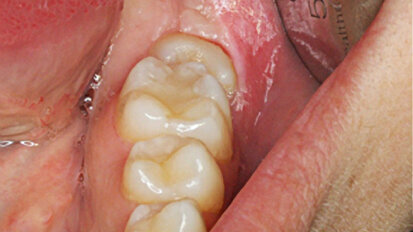

Tratamiento de segundo y tercer molar inferior “enclavados”

El autor presenta un caso de un segundo y tercer molar inferior enclavados, “diente retenido que ha perforado el techo óseo, con apertura del saco ...

Los terceros molares inferiores retenidos constituyen aproximadamente un 35% de las retenciones dentarias. Sin embargo, los segundos molares inferiores ...